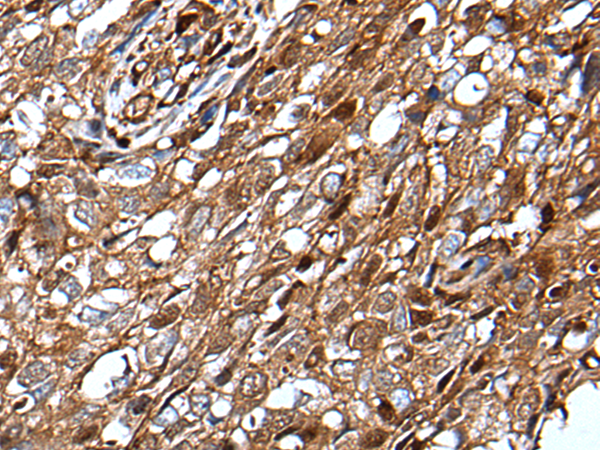

IHC positive control:

Human lung cancer

IHC Recommend dilution:

20-100